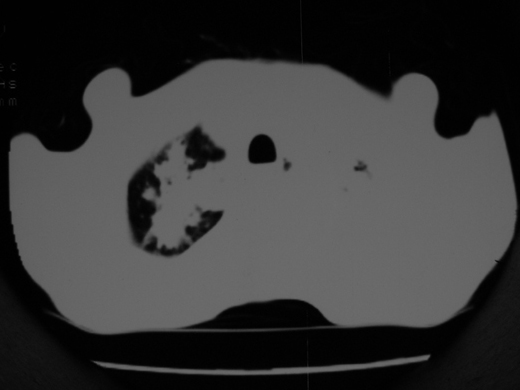

男69岁,年前胸片示肺感染治疗近一月今复查无明显好转,血象正常

右肺多发片絮状结节状及时条索状影,左上肺实变,内可见虫蚀样空洞及支气管气象,左下肺片状及球形病灶,及胸腔积液征象,双肺病灶内多发钙化影,结合病史,考虑双肺继发型肺结核,左胸腔积液

右肺多发片絮状结节状及时条索状影,左上肺实变,内可见虫蚀样空洞及支气管气象,左下肺片状及球形病灶,及胸腔积液征象,双肺病灶内多发钙化影,上纵隔向左侧移位,结合病史,考虑双肺继发型肺结核,左胸腔积液。

考虑双肺支气管内膜结核并左侧肺不张,左胸腔积液可能性大建议气管镜检查或抗结核治疗隔期复查

右肺多发片絮状、结节状及条索状影,左上肺实变,内可见虫蚀样空洞及支气管气象,左下肺片状及球形病灶,有胸腔积液征象,双肺病灶内多发钙化影,上纵隔向左侧移位,结合病史,考虑双肺继发型肺结核,左胸腔积液。 建议结合ppd检查或纤支镜检查!

双肺结核,左肺实变。左侧胸腔积液(部分包裹)。

右肺可见大片状、云絮状改变。右肺可见散在类圆形影,以外带多见。左肺实变,其内可见明显支气管走行影。纵隔淋巴结有增大,左侧胸腔积液。考虑1、肺结核;2、肺癌肺转移不除外;3、左侧胸腔积液。